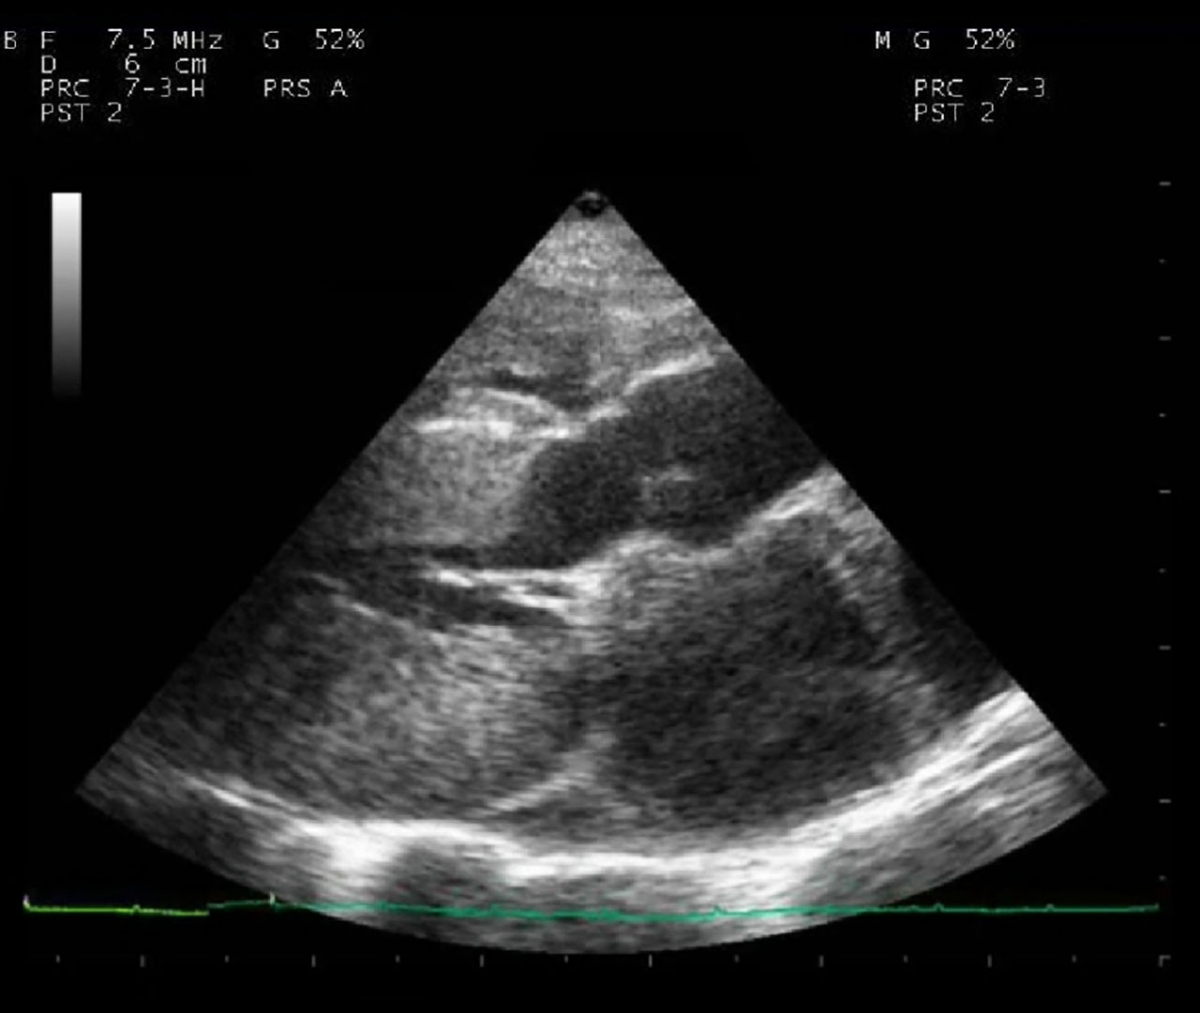

Exploring HCM Testing in Cats Cat Reign

Exploring HCM Testing in Cats Cat Reign What Causes Hcm In Cats Web hypertrophic cardiomyopathy is the most commonly diagnosed cardiac disease in cats. Hcm causes the heart muscle to become. Hypertrophic cardiomyopathy (hcm) is the most commonly diagnosed cardiac disease in cats. How is hcm in cats diagnosed? What are the symptoms of hcm in cats? Web hypertrophic cardiomyopathy (hcm) is the most common type of heart disease found in cats.. What Causes Hcm In Cats.

Exploring HCM Testing in Cats Cat Reign What Causes Hcm In Cats Web what causes hcm? Hypertrophic cardiomyopathy (hcm) is the most commonly diagnosed cardiac disease in cats. Web what causes hcm in cats? Web hypertrophic cardiomyopathy (hcm) is the most common form of feline cardiomyopathy observed clinically and. Hcm causes the heart muscle to become. How is hcm in cats diagnosed? What are the symptoms of hcm in cats? Web hypertrophic. What Causes Hcm In Cats.